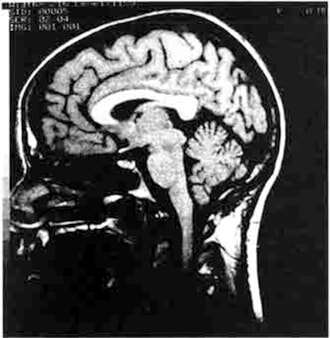

Actualmente, la tecnología de proyectar en imagen el cerebro está a distancia sideral del examen post mortem o autopsia que era la única alternativa al alcance de científicos y médicos en la época de Paul Broca. En el curso de apenas unos cinco años, para los neurólogos se ha vuelto común la posibilidad de obtener imágenes por CAT-scan del cerebro de seres vivientes, que en cuestión de minutos pueden mostrar las estructuras cerebrales desde cualquier nivel que se desee. Cientos de radiografías tomadas desde distintas direcciones alrededor de la cabeza son analizadas por computadora, y surge así una imagen del cerebro. Al paciente se le aplica una inyección intravenosa de una sustancia con un color que resalte, pero en todo otro sentido la imagen por CAT-scan se obtiene sin interferir físicamente en modo alguno con la materia cerebral. En una tecnología más nueva denominada imagen de resonancia magnética (MRI), el empleo de una combinación del campo magnético y energía de radioonda hace que sea innecesaria la inyección de una tintura. La calidad de las imágenes MRI es asombrosa (figura 10). Ya no es necesario correr los riesgos de una neurocirugía exploratoria para localizar tumores cerebrales y otros trastornos neurológicos.

Figura 10. Visión lateral, producida por imagen de resonancia magnética (MRI), de un cerebro humano vivo e intacto. (General Electric Medical System.)